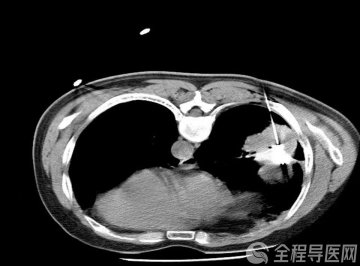

82岁的李奶奶,突然出现乏力、恶心、呕吐、食欲不振、厌油腻食物,并伴有尿色深黄如浓茶样,眼睛和皮肤也明显变黄。家人见状,迅速送往附近医院,经化验,李奶奶谷丙转氨酶升高至了正常上限的40倍,总胆红素也升至正常上限的10多倍,而凝血酶原活动度(判断肝衰竭的关键指标之一)降至了35%,戊型肝炎抗体IgM呈阳性,医生迅速给出了诊断:急性戊型肝炎、肝衰竭。当地医院迅速将患者转至北京地坛医院徐州医院。